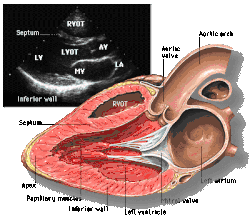

![]() Parasternal long axis |

| Each figure contains a TTE with a black background, and a corresponding colored illustration. | Patrick J. Lynch and C. Carl Jaffe, Yale University, 2006. | ||||||||||

| Click on a figure to enlarge it and see some parts of the heart identified. RV, right ventricle; LV, left ventricle; RA, right atrium; LA, left atrium; TV, tricuspid valve; MV, mitral valve; AV, aortic valve; RVOT, right ventricular outflow tract; LVOT, left ventricular outflow tract | |||||||||||